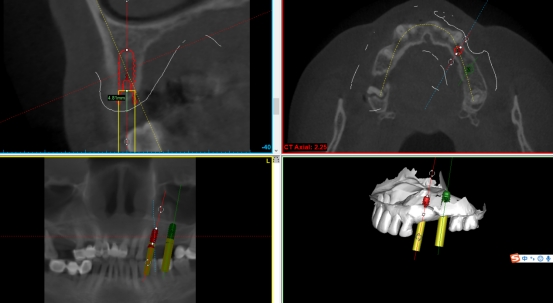

数字化种植导板是通过导板设计软件对CBCT、口扫等一系列数据的系统性分析,辅助口腔种植位点的设计,然后通过3D打印技术等途径进行导板生产,从而实现精准定位的种植手术装置。

简单来讲,数字化种植外科导板(简称导板),是将术前软件设计的种植方案,精确转移至患者口内的个性化手术辅助配件。

在数字化种植导板下,通过CBCT、口扫等途径获取口腔三维信息内容。使患者在种植之前就可以了解到种植方案的相关细节,清晰地看到牙齿修复之后的模拟展示图,提前预知种植术后的效果。

二、精准控制 更安全

在数字化种植导板下的外科手术更加精准。种植体植入方向、位置、角度、深度等一目了然,即可将种植体精准植入到最佳位置,获得更优异的临床效果,手术安全性更高。